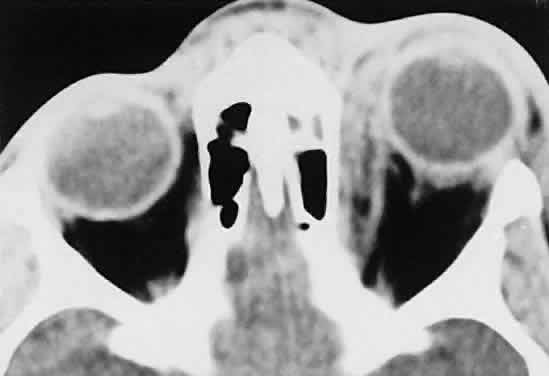

Within the orbit, rhabdomyosarcoma occurs most often, but not exclusively, in the superior nasal quadrant, with downward and outward displacement of the globe. CT scans show the topography of the orbital mass (Fig. 1A), as well as the possible extension into adjacent bone, paranasal sinuses, or the intracranial cavity. The circumscription that may be noted on CT is relative, because the lesion is not encapsulated and microscopically infiltrates normal tissue. Echography shows internal echoes of low-to-medium amplitude. Because the cellular tumor absorbs acoustic energy, the amplitude of the spikes falls off somewhat through the lesion (see Fig. 1B and C). MRI can help define the tumor's relationship to extraocular muscles (Fig. 2).

Fig. 1. A. Proptosis and downward, outward globe displacement developed over 2 days in a 3-year-old girl. A homogeneous mass fills the superomedial orbit. B. Contact B-scanning shows a relatively well-circumscribed mass with uniform internal echoes. C. Contact A-scanning shows the internal reflectivity to be of low to medium amplitude, consistent with a sarcomatous lesion. Biopsy results confirmed the diagnosis of rhabdomyosarcoma.

Fig. 2. MRI shows an intraconal tumor of lower intensity than the medial rectus muscle. The proximal muscle is splayed rather than compressed, suggesting that the lesion originated within the medial rectus. The diagnosis was alveolar rhabdomyosarcoma.